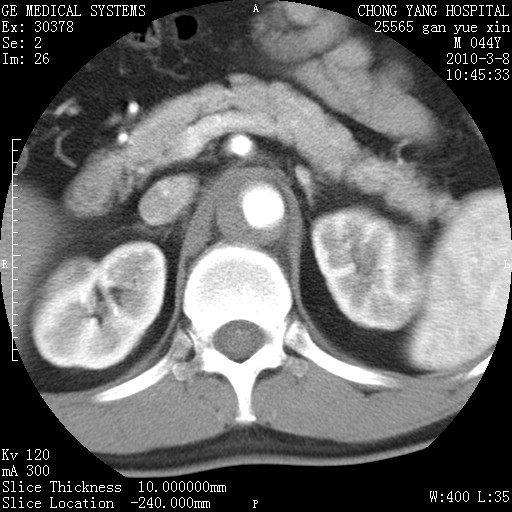

标题: CT24940:主动脉增强,典型病例。 [打印本页]

标题: CT24940:主动脉增强,典型病例。

夹层动脉瘤。

动脉夹层

夹层动脉瘤,典型

主动脉夹层。

动脉夹层的分型:

⒈debakey分型:根据主动脉夹层累及部位,分为三型:ⅰ型:原发破口位于升主动脉或主动脉弓部,夹层累及升主动脉、主动脉弓部、胸主动脉、腹主动脉大部或全部,少数可累及髂动脉。ⅱ型:原发破口位于升主动脉,夹层累及升主动脉,少数可累及部分主动脉弓。ⅲ型:原发破口位于左锁骨下动脉开口远端,根据夹层累及范围又分为ⅲa,ⅲb。ⅲa型:夹层累及胸主动脉。ⅲb型:夹层累及升主动脉、腹主动脉大部或全部。少数可累及髂动脉。

⒉stanford分型:a型:夹层累及升主动脉,无论远端范围如何。b型:夹层累及左锁骨下动脉开口以远的降主动脉。

夹层动脉瘤,少量胸水

夹层动脉瘤;左侧少量胸腔积液。

典型主动脉夹层。